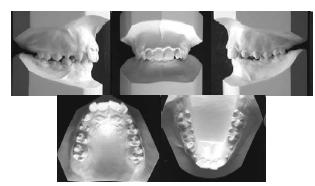

As figuras apresentadas acima apresentam os moldes das arcadas dentárias de um paciente. Assinale a opção correta quanto à fase da dentição em que o paciente se encontra e o tipo de má oclusão apresentado, de acordo com a classificação proposta por Angle.